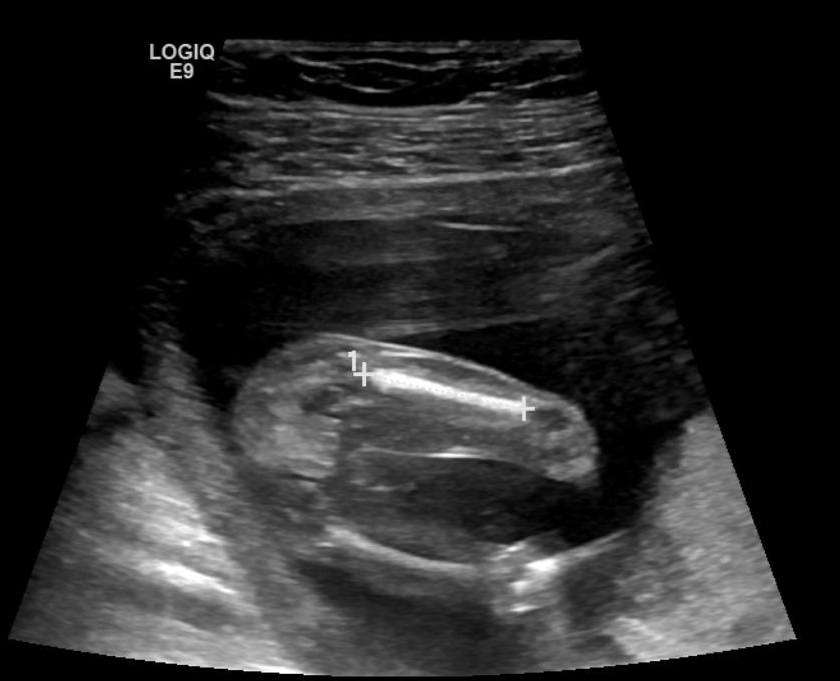

These all looks boy shots don't they, I'm in denial & clutching at straws here after trying for a girl ... Looks like 3 boys for us !

Forgot to mention measuring 15 weeks 3 days

Looks very boyish to me.

Yes, I hate to say it but it's looking very promising for another little boy.

Yes that looks like a willy. Did you try to sway for a girl?

That's a boy. I'm sorry you didn't hear pink.